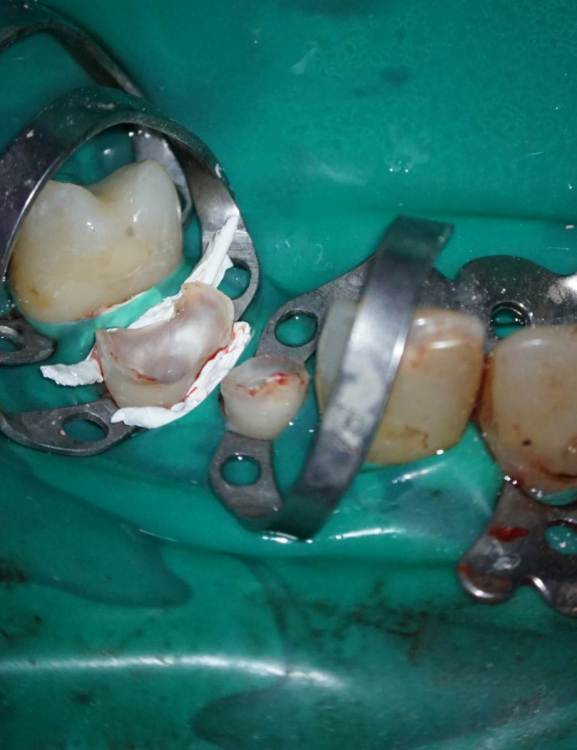

TIGER Опубликовано 3 ноября, 2023 Поделиться Опубликовано 3 ноября, 2023 Периохирургия способна на чудеса)не спешите удалять зубы 5 1 Ссылка на комментарий

АнтонТЛТ Опубликовано 3 ноября, 2023 Поделиться Опубликовано 3 ноября, 2023 Ну раз 12 удлинял, то можно было удлинить с аркой зенита и сделать как 22 Ссылка на комментарий

TIGER Опубликовано 3 ноября, 2023 Автор Поделиться Опубликовано 3 ноября, 2023 @АнтонТЛТ Антон честно,лень было)Пациентка довольна как слон,эстетические требования приемлимые.Поэтому не стал навязывать доп манипуляцию.Поэтому тут считаю результат приемлимый Ссылка на комментарий